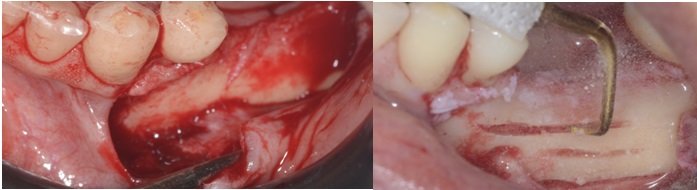

Demarcação da osteotomia retangular através de orifícios feitos com fresa cirúrgica esférica para peça reta ou uso do piezo surgery é mais indicado (Fig 6). Normalmente marcamos 3 mm acima e abaixo do forâmen mentoniano e a extensão do retângulo deve ir além da marcação do ultimo implante distal.

Quanto maior a janela retangular menor será a manipulação do nervo alveolar inferior, consequentemente a sensibilidade do nervo será menos alterada.

Remoção do osso vestibular com um cinzel curvo para ter acesso ao nervo alveolar (Fig 7).

Osteotomia óssea ao redor do foramen mentoniano para liberação total do nervo.

Depois da remoção do bloco ósseo retiramos o osso medular com curetas de Lucas ou molt até a completa visualização do nervo alveolar.